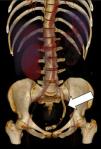

Mujer de 28 años con A. P.: esclerosis múltiple, vejiga neurógena e infecciones urinarias de repetición; sondaje vesical intermitente. Consulta por malestar general y fiebre de 38,8° C. Ingresa en UCI por sepsis grave. Se realiza ecografía abdominal que muestra patología renal izda. y TAC abdominal: vejiga con sonda e imagen alargada hiperdensa de gran tamaño que comunica con contenido hiperdenso en uréter distal izquierdo (fig. 1) (la flecha indica el cuero extraño en el interior del uréter izquierdo). Severa uretero-hidronefrosis del mismo lado y colección perirrenal con extensión a espacio subfrénico y apertura del grupo calicial superior que se comunica con el absceso. Compatible con pionefrosis con pequeños abscesos en parénquima renal y gran colección abscesificada perirrenal (fig. 2) (la flecha indica el absceso perinéfrico izquierdo). Se interpretó que la imagen en el uréter izquierdo correspondía a un cuerpo extraño, probablemente una sonda vesical introducida en alguno de los sondajes que se realizaba la paciente, rota y alojada en el uréter de forma inadvertida produciendo la uretero-hidronefrosis y los abscesos renales, como se comprobó tras la extracción de la misma. Evolución inicial: shock séptico con fracaso multiorgánico. Se trató con antibióticos, extracción del cuerpo extraño (sonda vesical) y drenaje del absceso con radiología intervencionista, intubación y ventilación mecánica. Alta de UCI 20 días después del ingreso.